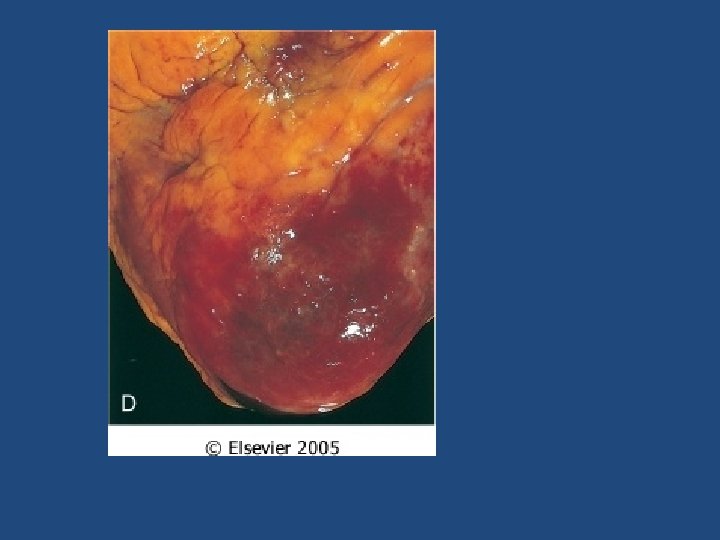

Ischemic Heart Disease Complications of MI • At least 80% will suffer: – Cardiogenic shock (>40% infarct of LV) – Congestive heart failure. CHF – Arrhythmia – Rupture of ventricle, free wall, septum, or papillary muscle – Aneurysm formation, – Mural thrombus, potentially source of emboli – Pericarditis

Ischemic Heart Disease Myocardial infarction • The severity or duration of ischemia is enough to cause cardiac muscle death • Typically results from acute thromboses that follow plaque disruption